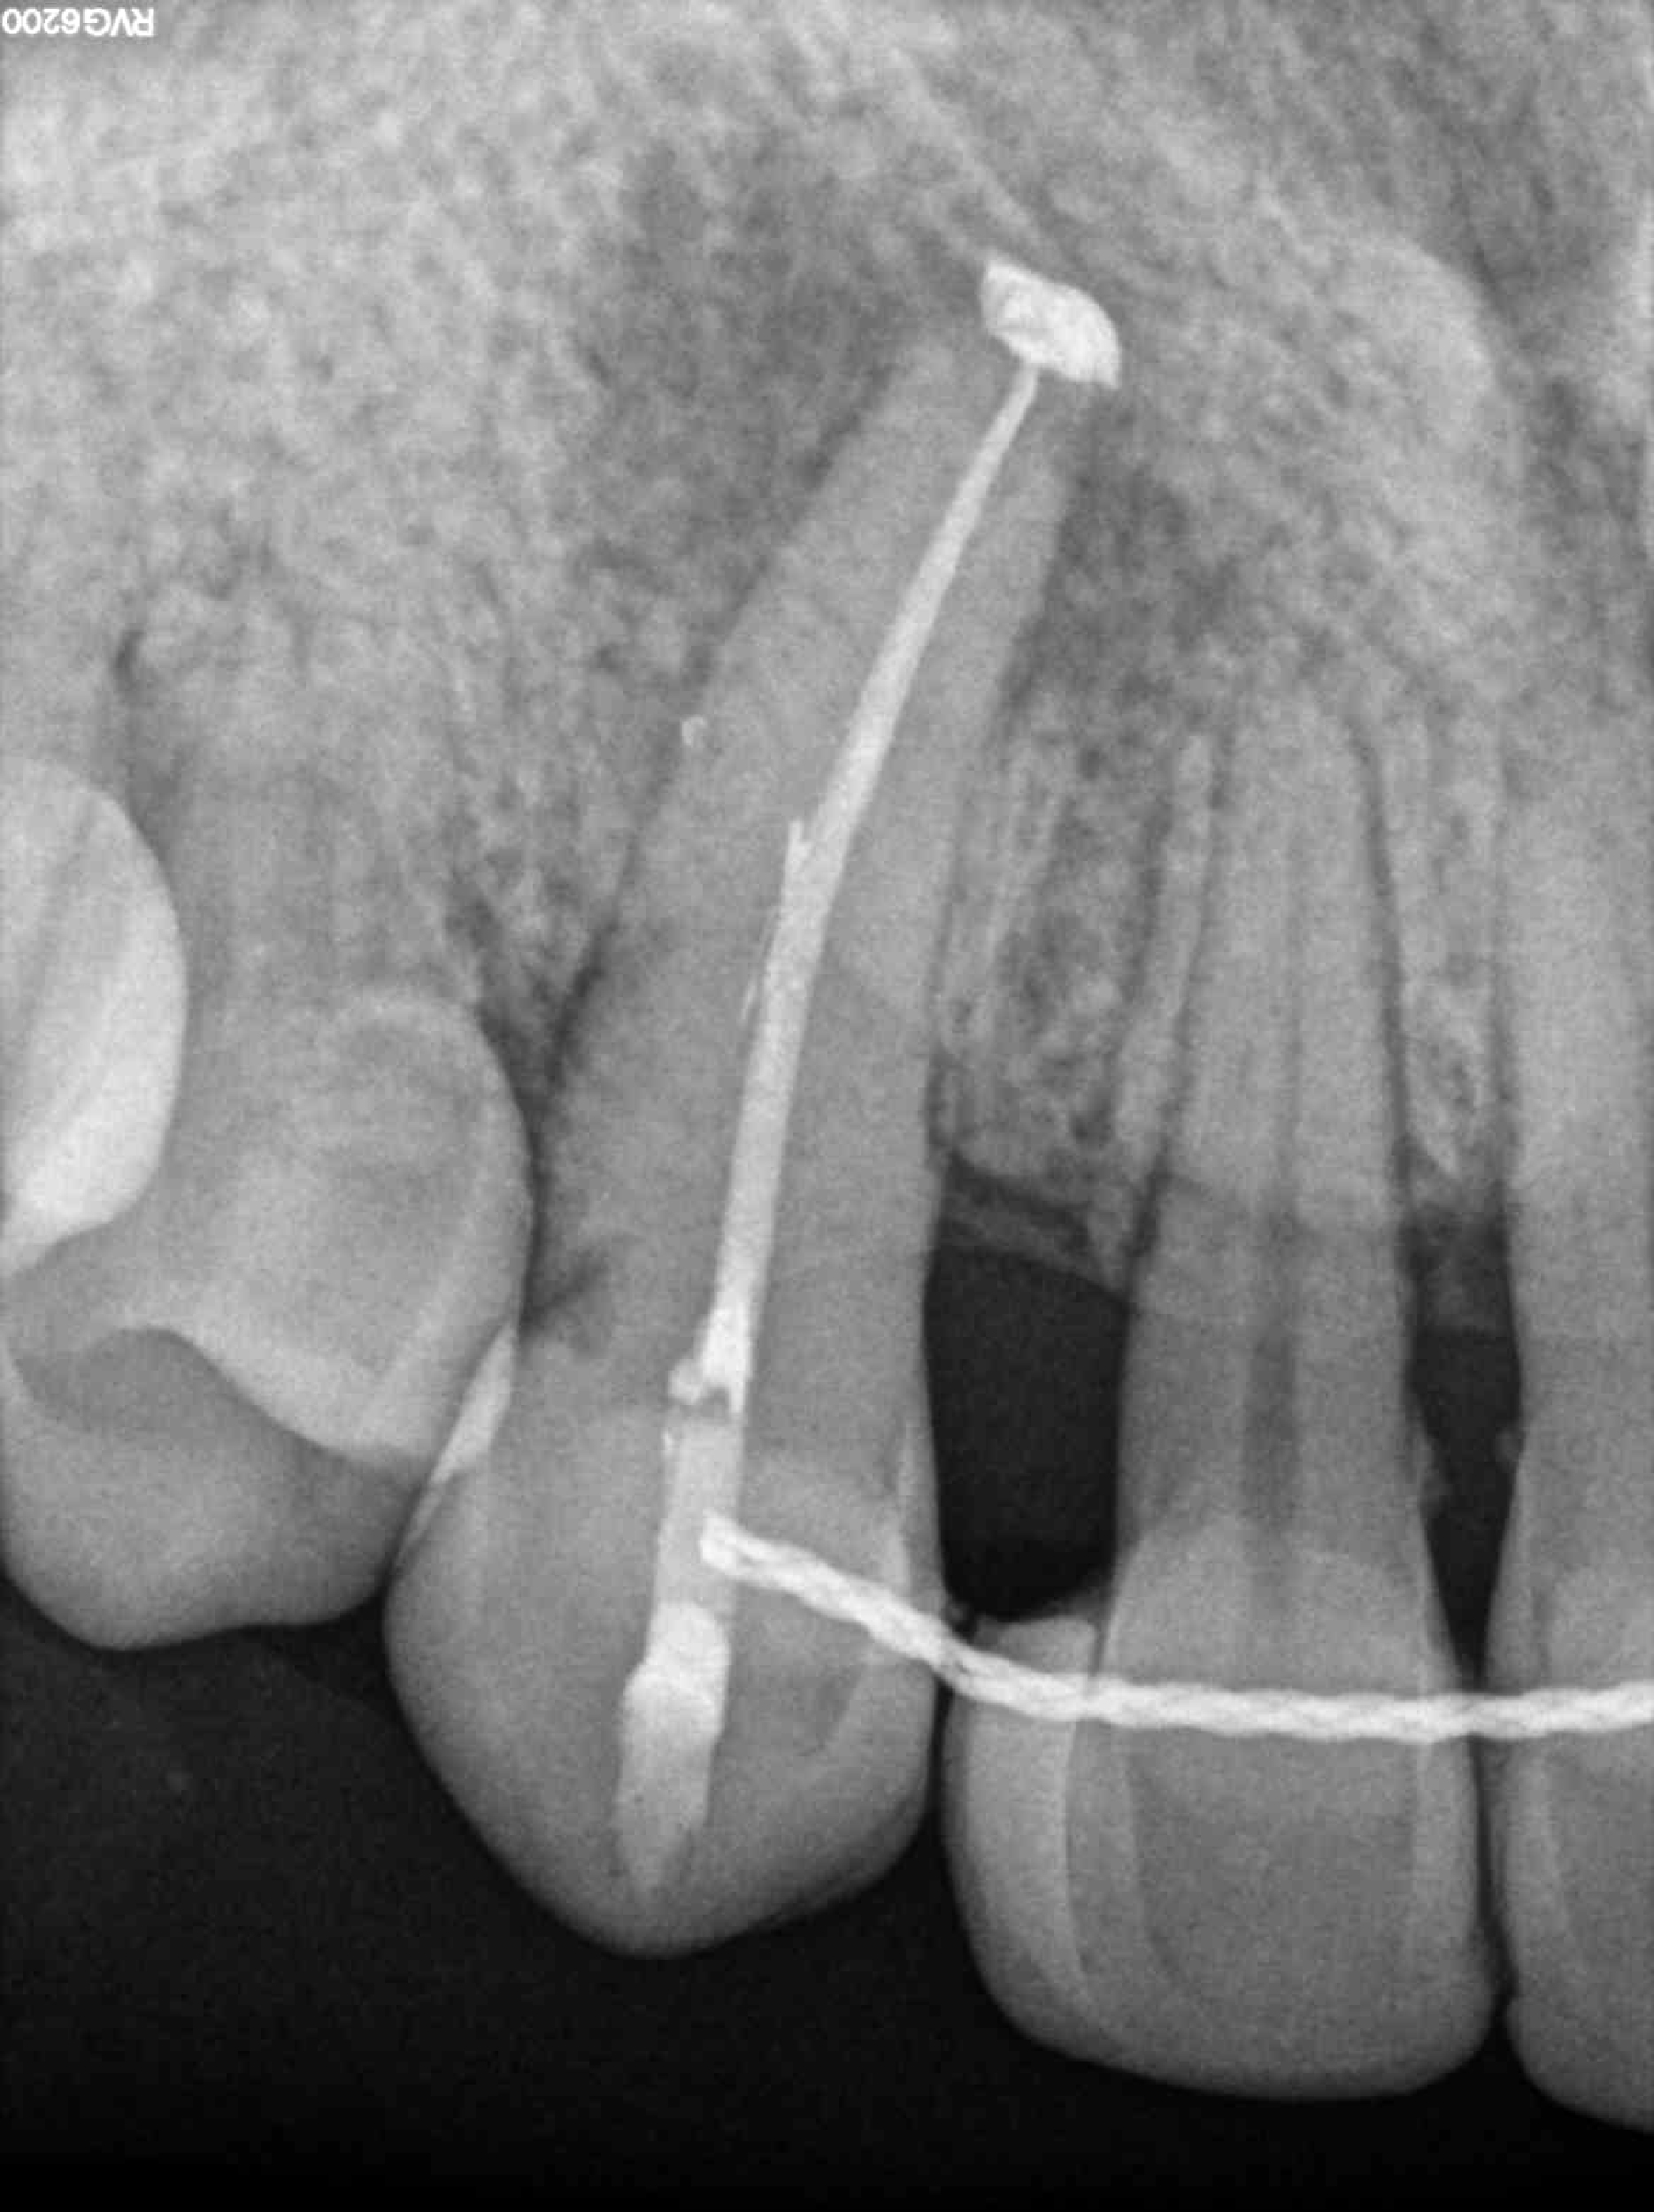

Radiografías

* Haz click sobre las radiografías para verlas a mayor tamaño